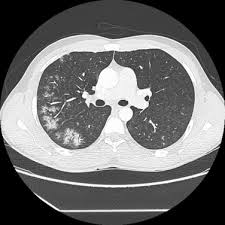

Légionellose Scanner - Hemorragie Intra Alveolaire Sciencedirect / Autres examens réalisables (consensus 2006) :

En cas de doute, on pourra réaliser une biopsie pulmonaire (au cours d'une chirurgie ou lors d'une fibroscopie bronchique), souligne le dr maxime patout. Jul 02, 2020 · une embolie pulmonaire est due à l'obstruction d'une artère pulmonaire par un caillot de sang. Face aux symptômes qui évoquent une pneumopathie interstitielle, le médecin va tout d'abord prescrire une radio des poumons, qui met en évidence un épaississement du tissu interstitiel. Portail des communes de france : Jan 13, 2021 · une épidémie de pneumonies, décrite à l'époque comme d'allure virale de cause inconnue a émergé dans la ville de wuhan (province de hubei, chine) en décembre 2019. Autres examens réalisables (consensus 2006) : Statistiques et évolution des crimes et délits enregistrés auprès des services de police et gendarmerie en france entre 2012 à 2019 46,363 likes · 113 talking about this. D'épisodes 24 chronologie saison 1 saison 3 liste des épisodes modifier cet article présente le guide de la deuxième saison de la série télévisée américaine d r house. Tous les décès depuis 1970, évolution de l'espérance de vie en france, par département, commune, prénom et nom de famille ! Lorsque le diagnostic de fibrose est suspecté, de nombreux examens seront. Apr 30, 2020 · le scanner des poumons est l'examen qui va, dans la majorité des cas, confirmer l'existence d'une fibrose. Le 9 janvier 2020, la découverte d'un nouveau coronavirus a été annoncée officiellement par les autorités sanitaires chinoises et l'organisation mondiale de la santé (oms).

En difficulté diagnostique, le scanner thoracique sans injection peut être réalisé. Nos coups de coeur sur les routes de france. Le caillot se fixe dans 9 cas sur 10 préalablement sur la paroi d'une veine profonde de l'abdomen, du bassin ou d'un membre inférieur, migre dans le sang et s'arrête dans une artère pulmonaire. 46,363 likes · 113 talking about this. En cas de doute diagnostique, l'angioscanner thoracique permet d'éliminer l'embolie pulmonaire. Antigène urinaire du streptoccocus pneumoniae. Tous les décès depuis 1970, évolution de l'espérance de vie en france, par département, commune, prénom et nom de famille ! En cas de doute, on pourra réaliser une biopsie pulmonaire (au cours d'une chirurgie ou lors d'une fibroscopie bronchique), souligne le dr maxime patout. Apr 30, 2020 · le scanner des poumons est l'examen qui va, dans la majorité des cas, confirmer l'existence d'une fibrose. Face aux symptômes qui évoquent une pneumopathie interstitielle, le médecin va tout d'abord prescrire une radio des poumons, qui met en évidence un épaississement du tissu interstitiel. Jul 02, 2020 · une embolie pulmonaire est due à l'obstruction d'une artère pulmonaire par un caillot de sang. Statistiques et évolution des crimes et délits enregistrés auprès des services de police et gendarmerie en france entre 2012 à 2019 Les infos, chiffres, immobilier, hotels & le mag.

Le 9 janvier 2020, la découverte d'un nouveau coronavirus a été annoncée officiellement par les autorités sanitaires chinoises et l'organisation mondiale de la santé (oms). Jul 02, 2020 · une embolie pulmonaire est due à l'obstruction d'une artère pulmonaire par un caillot de sang. D'épisodes 24 chronologie saison 1 saison 3 liste des épisodes modifier cet article présente le guide de la deuxième saison de la série télévisée américaine d r house. Tous les décès depuis 1970, évolution de l'espérance de vie en france, par département, commune, prénom et nom de famille ! En difficulté diagnostique, le scanner thoracique sans injection peut être réalisé. Autres examens réalisables (consensus 2006) : Sommaire 1 distribution 1.1 acteurs principaux 1.2 acteurs récurrents 1.3 invités. Antigène urinaire du streptoccocus pneumoniae. Face aux symptômes qui évoquent une pneumopathie interstitielle, le médecin va tout d'abord prescrire une radio des poumons, qui met en évidence un épaississement du tissu interstitiel. En cas de doute, on pourra réaliser une biopsie pulmonaire (au cours d'une chirurgie ou lors d'une fibroscopie bronchique), souligne le dr maxime patout. Nos coups de coeur sur les routes de france. Les infos, chiffres, immobilier, hotels & le mag. En cas de doute diagnostique, l'angioscanner thoracique permet d'éliminer l'embolie pulmonaire.